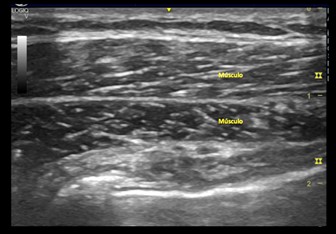

Imagen ecográfica 3.1 Eje longitudinal del músculo braquioradial.

En el plano transversal (perpendicular al musculo) el tejido muscular muestra un aspecto moteado debido a las reflexiones del tejido conjuntivo del perimisio, el cual es moderadamente ecogénico.

En músculos complejos, una vaina fascial hiperecogénica individual rodea a cada vientre muscular y de esta manera se pueden identificar las diferentes cabezas de un mismo musculo.

En el musculo hay un aumento de interfases reflectivas lo cual le da un aspecto más blanco en comparación con la grasa.  Como nota importante las interfases reflectivas de igual manera aumentan en enfermedades neuromusculares por el aumento de fibrosis, inflamación y grasa.